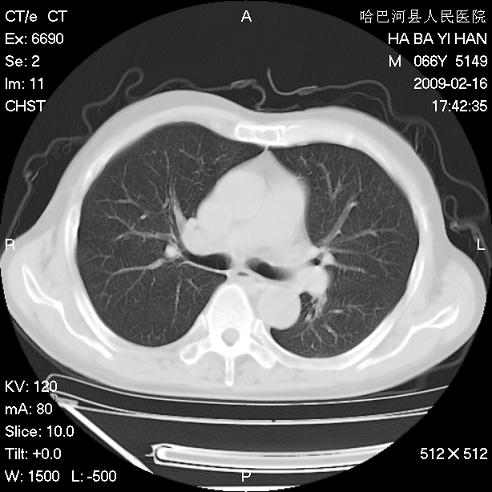

以下是引用huangxun4321在2009-2-16 20:18:00的发言:[br]部分病灶可见硬化边,部分可见骨质破坏消失,部分病灶内可见骨脊,说明病灶内既有良性病变,又有恶性病变,考虑骨巨细胞瘤恶变,未除骨纤恶变,畸形性骨炎少见,亦要考虑.

以下是引用731208在2009-2-16 20:31:00的发言:[br]考虑恶性胸膜间皮瘤并肋骨,脊柱转移。

以下是引用yijiansheng在2009-2-16 20:16:00的发言:[br]考虑恶性胸膜间皮瘤并肋骨,脊柱转移。

以下是引用形影不离在2009-2-16 19:55:00的发言:[br]考虑多发性转移瘤。